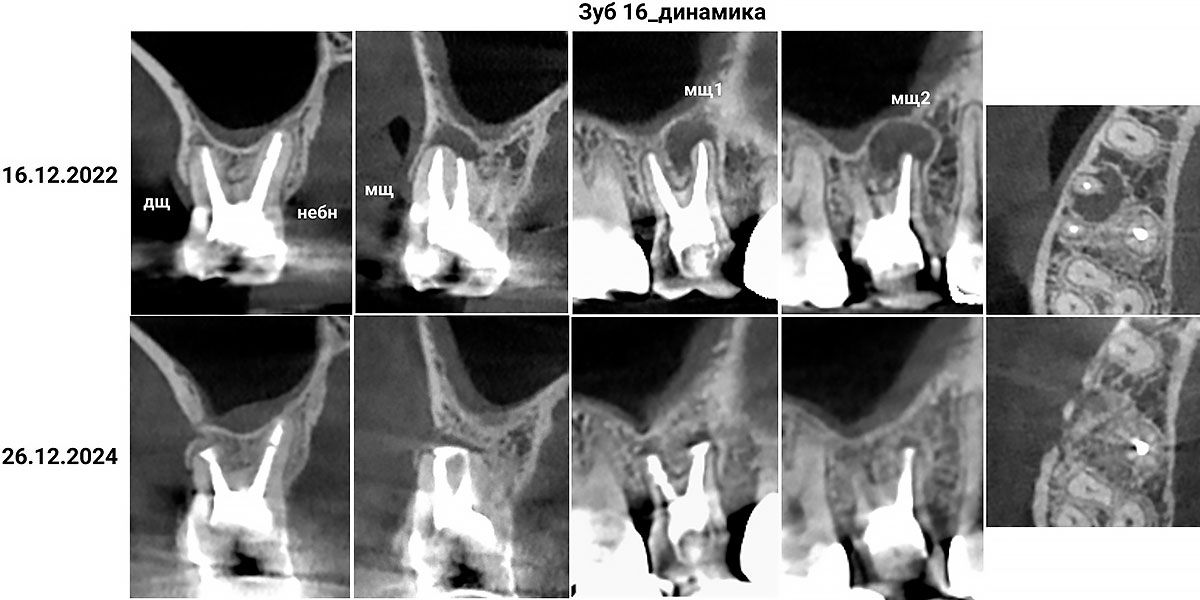

Пациентка Н. обратилась в мае 2023 г. с жалобами на периодические болевые ощущения в области жевательного зуба вверху справа. Анализ конусно-лучевой компьютерной томографии (КЛКТ) зубных рядов с помощью искусственного интеллекта (рис. 0) выявил наличие деструкции костной ткани в области верхушки мезиального корня зуба 1.6 с четкими контурами, при рентгенологически качественной обтурации корневых каналов (рис. 1). Такая картина не редка при необработанном перешейке между корневыми каналами, что крайне затруднительно при ортоградном доступе. При этом искусственная коронка изготовлена несколько лет назад.

В динамике ИРЗ от 27 ноября 2023 представлена на рис. 8. В рамках ежегодной дентальной диспансеризации выполнена КЛКТ от 29 ноября 2023, на которой визуально отмечается наличие очагов радиолюценции в области верхушек щечных корней зуба 1.6 (по срокам соответствует периоду формирования слабо минерализованной костной ткани). В динамике на КЛКТ от 26 декабря 2024 визуально отмечаются признаки почти полного ее восстановления. Жалобы пациентки исчезли в ранние сроки после проведенной зубосохраняющей манипуляции и больше не проявлялись.